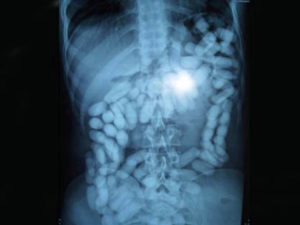

Les suspects ont été placés sous surveillance médicale au Centre hospitalier universitaire Ibn Rochd pour extraire les capsules de leurs intestins, a ajouté la même source, précisant que l’opération a permis la saisie de 2,985 kilogrammes de cocaïne mise dans 162 capsules.